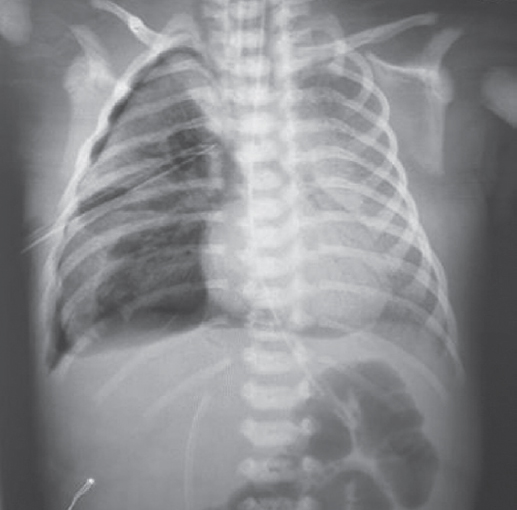

Состояние ребенка с рождения средней степени тяжести, обусловленное явлениями респираторного дистресса (умеренное втяжение межреберий, стонущее дыхание, тахипноэ до 60 в минуту), что потребовало проведения неинвазивной искусственной вентиляции легких (ИВЛ, nСРАР — nasal continuous positive airway pressure) c первых минут жизни [2]. На рентгенограмме отмечаются признаки транзиторного тахипноэ новорожденного (рис. 1).

Рис. 1. Рентгенограмма органов грудной клетки новорожденного с клиническими признаками респираторного дистресс-синдрома через 2 ч после рождения

Fig. 1. Chest X-ray of newborn with clinical signs of respiratory distress 2 hours after birth